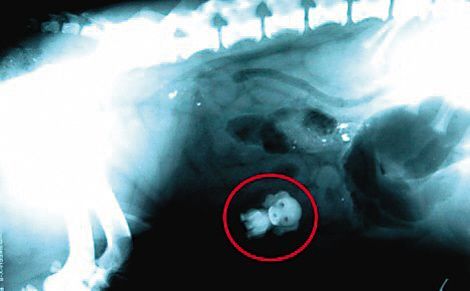

用X射线成像技术拍摄物体